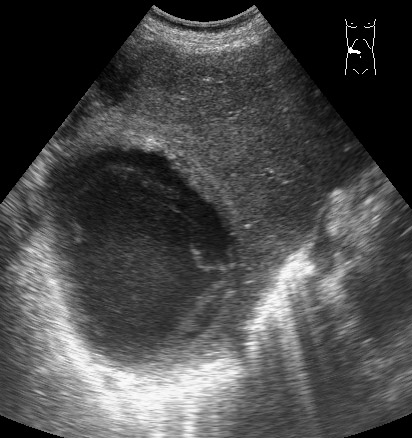

#2

10-04-09-145915_2903_201004.jpg

Типичная картина ##1-4:

Гипоэхогенное неоднородное округлое образование, окруженное эхогенным "демаркационным валом"

измененной паренхимы печени.